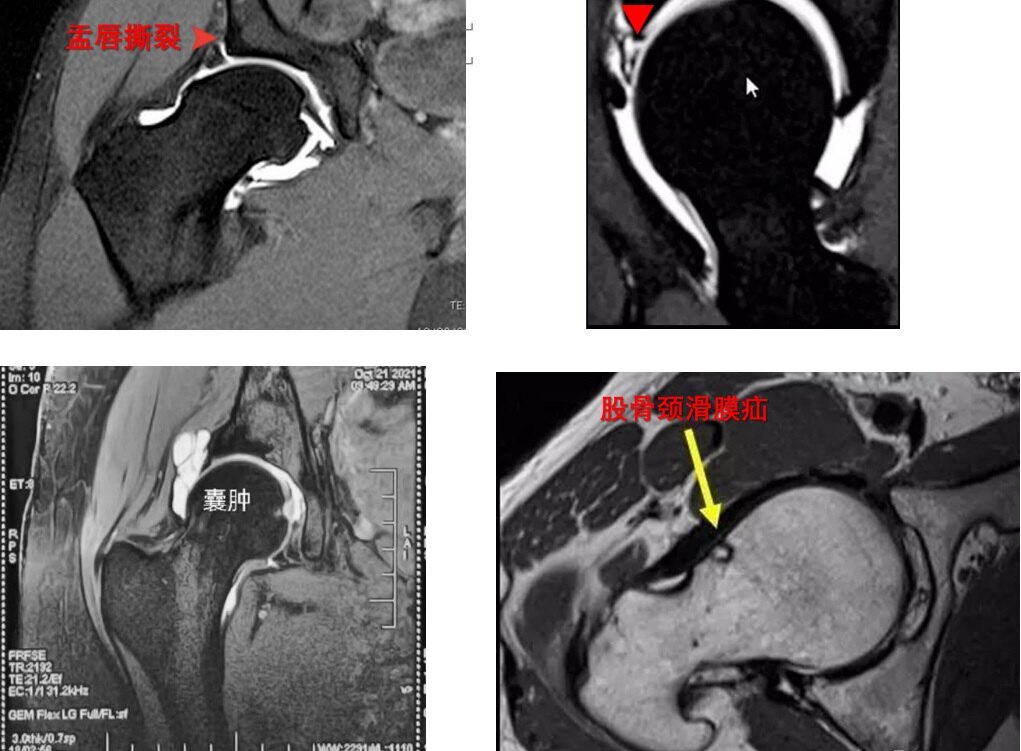

(3)磁共振:(单髋3.0T):盂唇损伤撕裂,囊肿,滑膜疝。(斜矢状位、斜冠状位、横轴位)

图15.患髋磁共振可评估盂唇损伤的程度和囊肿形成的情况。

(2) 髋关节盂唇损伤:髋关节周围“C”形区疼痛、活动受限。

盂唇(labrum)附着于髋臼缘,像一个“皮搋[chuāi]子(马桶疏通器)”,在关节内少量关节液形成负压的条件下,可以吸住股骨头,防止股骨头脱位。

盂唇感觉神经分布丰富,髋关节撞击损伤盂唇,导致髋关节周围“C”形区疼痛,髋关节活动受限。